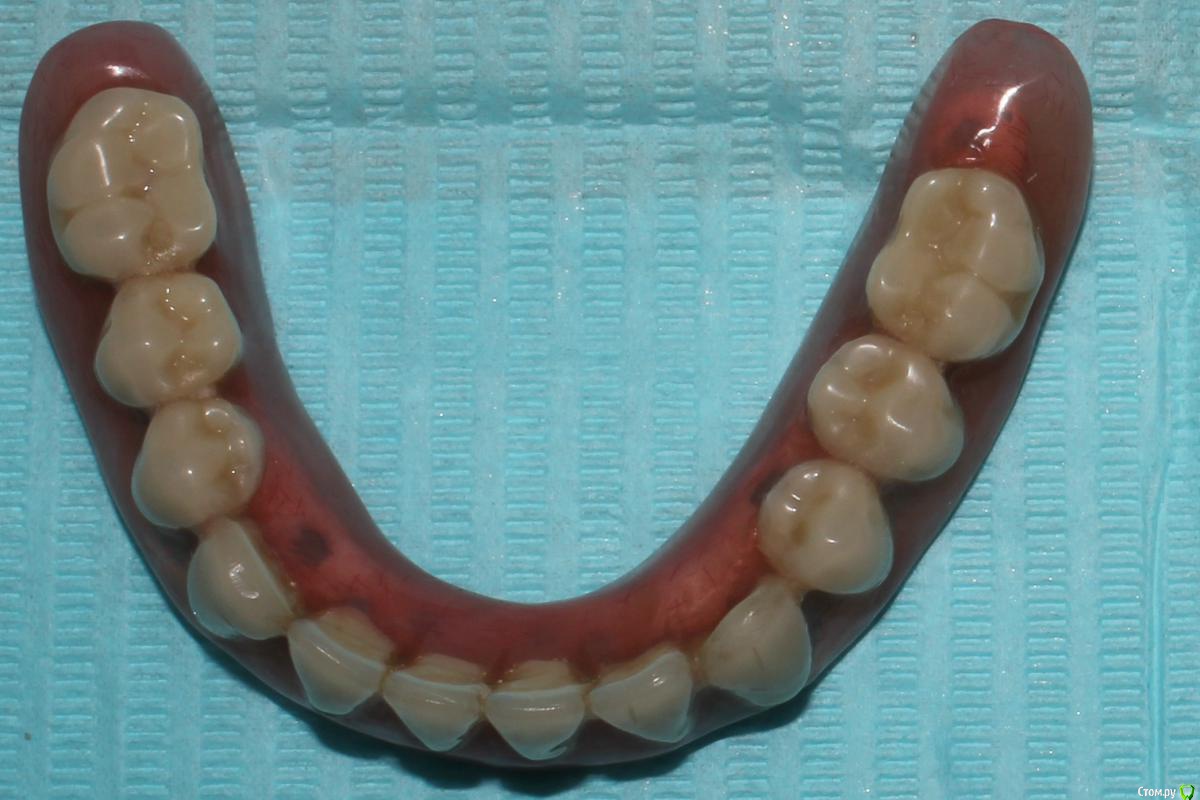

Larnary Опубликовано 1 февраля, 2016 Поделиться Опубликовано 1 февраля, 2016 (изменено) Обычные Бреденты(или аналог) на вкладках. Реализация идеи ненадежная. Что касается протеза на нижнюю челюсть.Правильнее было бы сделать в протезе литую балку и вставить в нее матрицы. Изменено 1 февраля, 2016 пользователем Larnary Ссылка на комментарий

Ronin Опубликовано 1 февраля, 2016 Поделиться Опубликовано 1 февраля, 2016 У меня это просто культевые аттачменты по типу бредента, как упомянули ранее)) иногда приходится делать, когда финансы не позволяют разгуляться на другие виды конструкций или в свете атрофии и сопутствуещей патологии.. Зато лучше, чем просто съемник при диабете или частичный. А по поводу фиксации самих замков, то как вкладки, если нормально ставить, соблюдая протокол, то ничего не вылетает))) Ссылка на комментарий